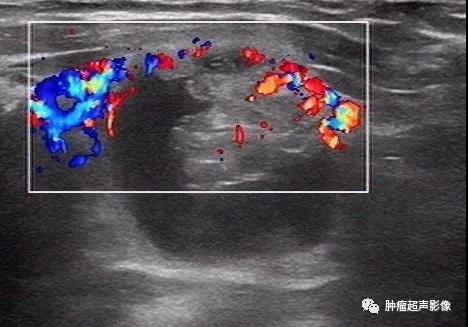

4、CDFI:实性部分丰富动脉血流,尤其是由中心向四周发出的分支动脉血流特异性较高(“烟花征”)。

来自微信会诊病例:形态不规则,微钙化,实性部分向周边的壁伸出多个较细的分隔(“蜘蛛征”),血流由中心向四周发出的分支动脉血流(“烟花征”)符合典型囊性乳头状癌,术后病理证实为乳头状癌